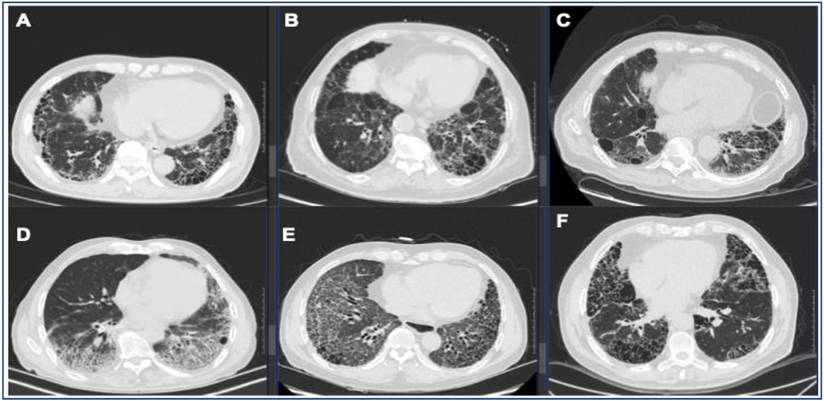

Representative UIP pattern on HRCT in IPF and secondary UIP. (A) IPF, (B) fHP, (C) RA-ILD, (D) pSS-ILD, (E) SSc-ILD, (F) AAV-ILD. Radiologic UIP pattern is defined as basilar, subpleural distribution of reticulation and traction bronchiectasis with honeycombing and without features incompatible with UIP.